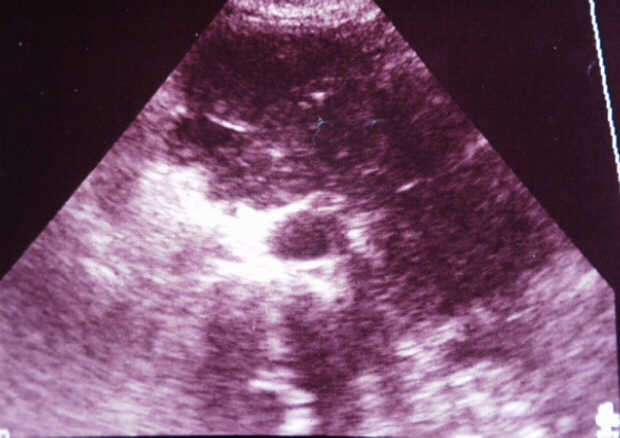

Diagnosis: Angiography

Giuseppe Morelli Coppola, Raffaella Niola, Franco Maglione

Unità Operativa di Radiologia Vascolare ed Interventistica, Azienda Ospedaliera "A. Cardarelli". Napoli, Italy